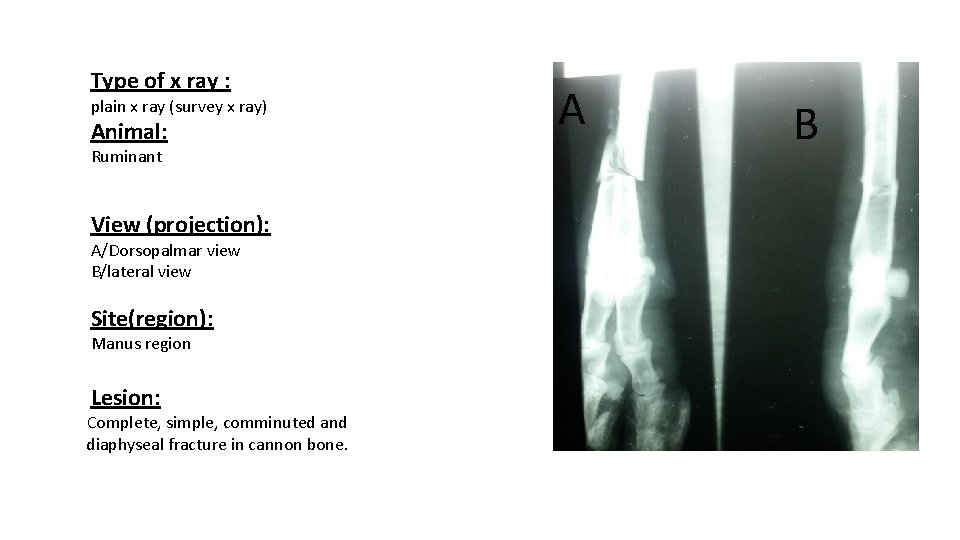

Type of x ray : plain x ray (survey x ray) Animal: Ruminant View (projection): A/Dorsopalmar view B/lateral view Site(region): Manus region Lesion: Complete, simple, comminuted and diaphyseal fracture in cannon bone. A B